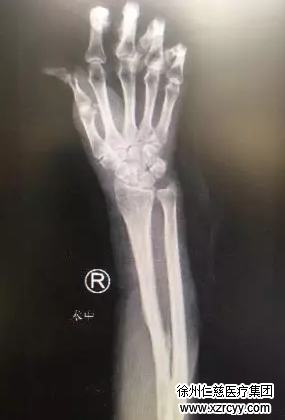

从一两年前开始,孙女士的右手腕处就开始莫名的疼痛,有时候还会有液体渗出,前段时间摔了一跤用右手撑住了地,之后右腕就更疼痛,甚至溃烂了一个指甲盖大小的伤口,一直难以愈合。刚开始一直不知道什么原因,后来去医院拍片子才发现原来是十几年前骨折时,在医院固定的钢针出了问题,本该半年就取出来的钢针,竟然在孙女士身体里存在了10多年。从X光片上清晰的看到,右腕处这一端钢针顶端弯曲的地方,刺破了肌肉和皮肤。

前臂钢针内固定的X线片